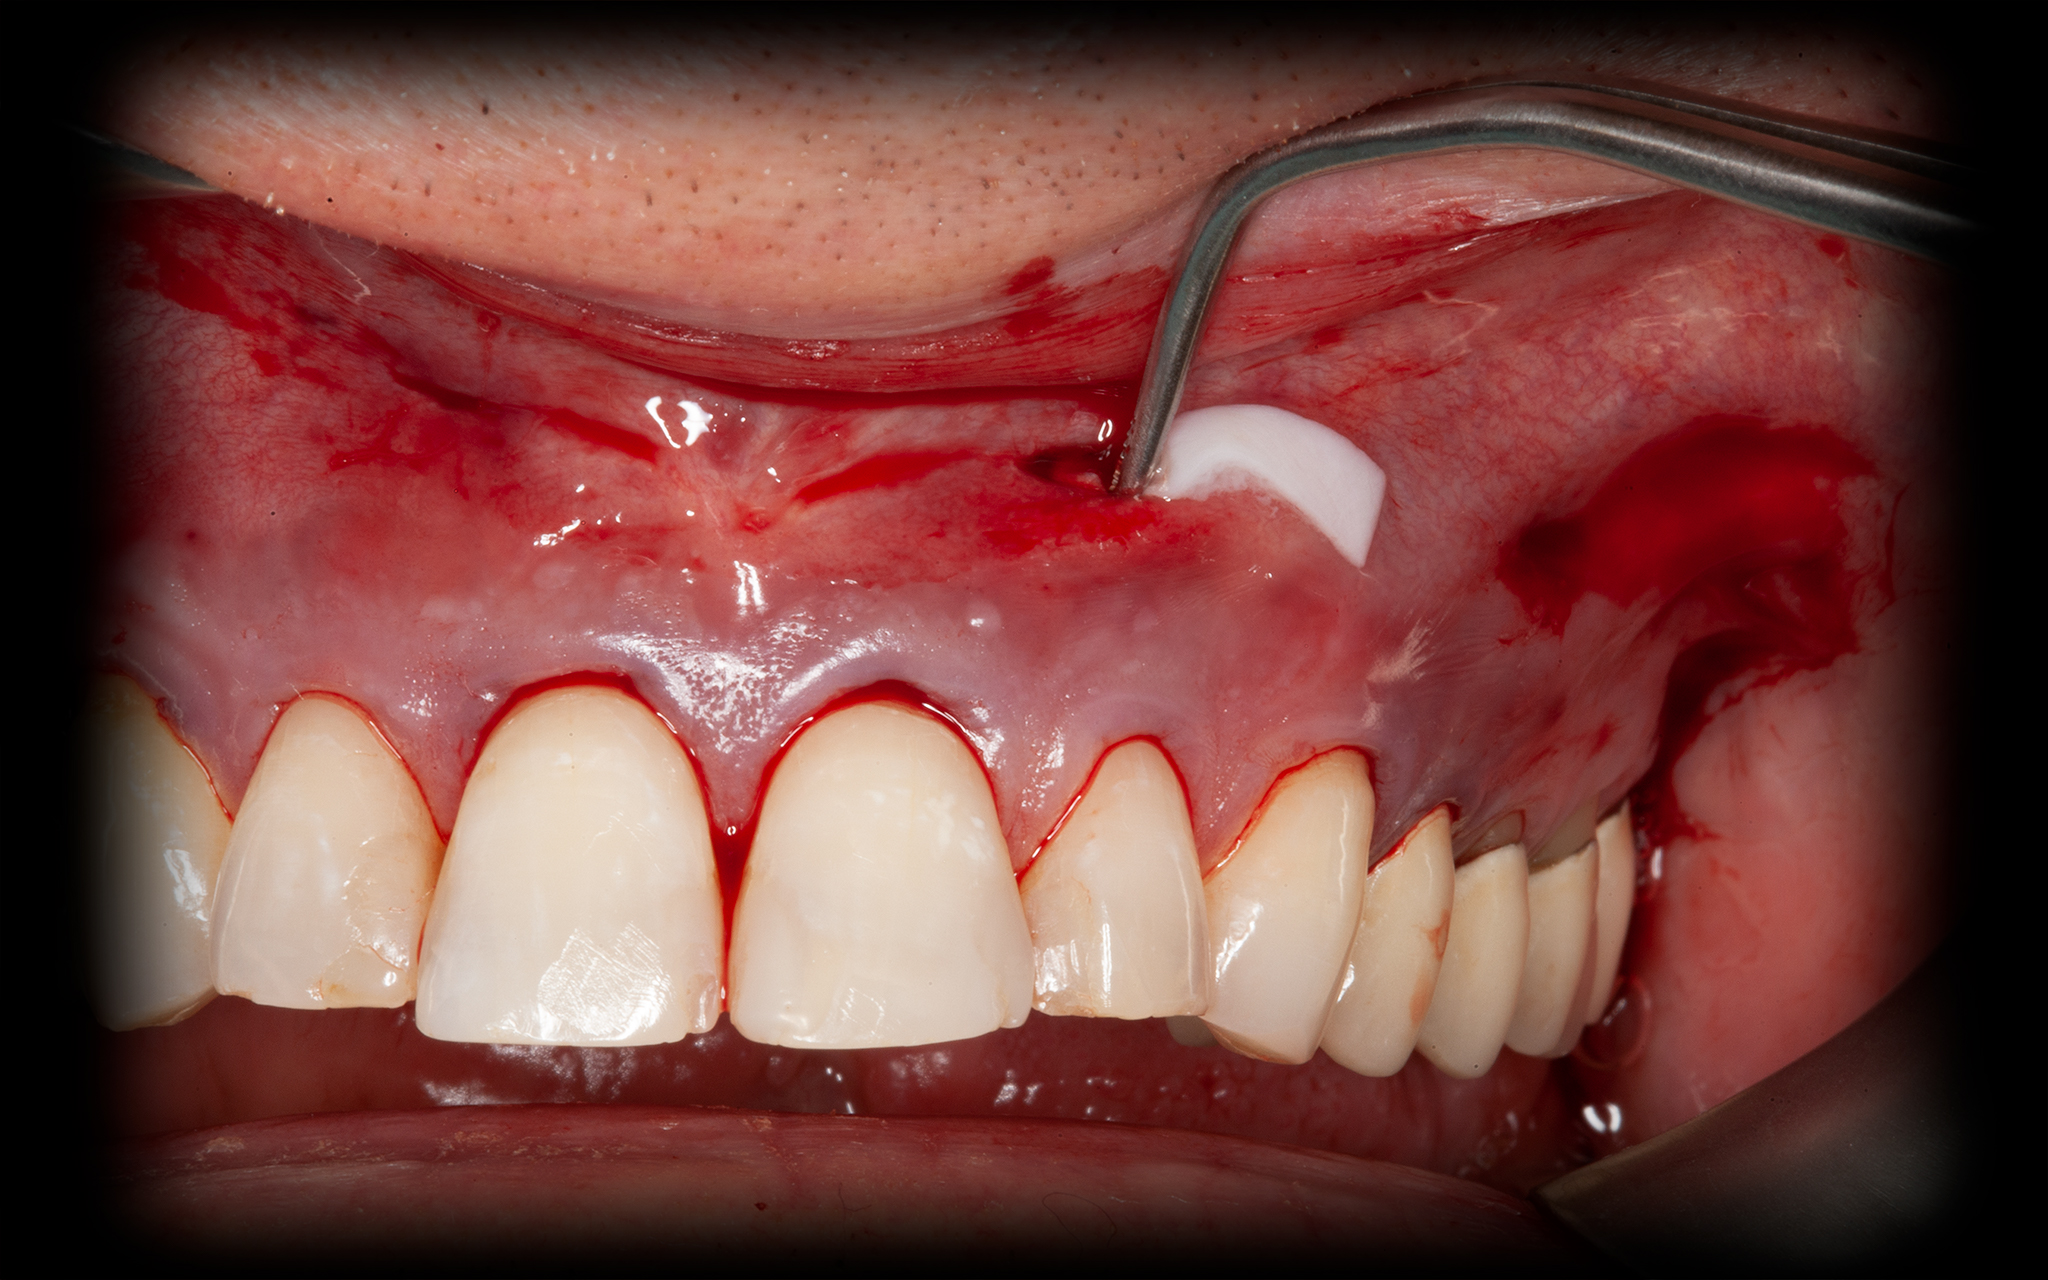

Operationsbilder Auch Operationsbilder anzeigen

• Zahnfleischaufbau, Deckung der freiliegenden Zahnhälse mit Bio-Material

Abdeckung der freiliegenden Zahnhälse (Rezessionsdeckung)

Rezessionen liegen bei ca. 25 Prozent der Patienten ab 40 Jahren vor. Mehrere Rezessionen in einer Behandlung zu decken bedeutet immer einen erhöhten Aufwand und eine umfassende Planung. Moderne Materialien ersparen uns in bestimmten Fällen die Gewebeentnahme aus dem Gaumen. Die Rezessionsdeckungen nach Art der „Pinhole Technique“ ist ein dieser Techniken. Der Gewebeersatz erfolgt mit Kollagenstreifen. Der Erfolg hängt von den anatomischen Voraussetzungen und dem Ausmaß der Rezession ab. Die Erfolgsrate bei diesen mikrochirurgischen Behandlungen liegt bei 85-100 Prozent. Die vollständige Heilung bedarf einige Wochen.